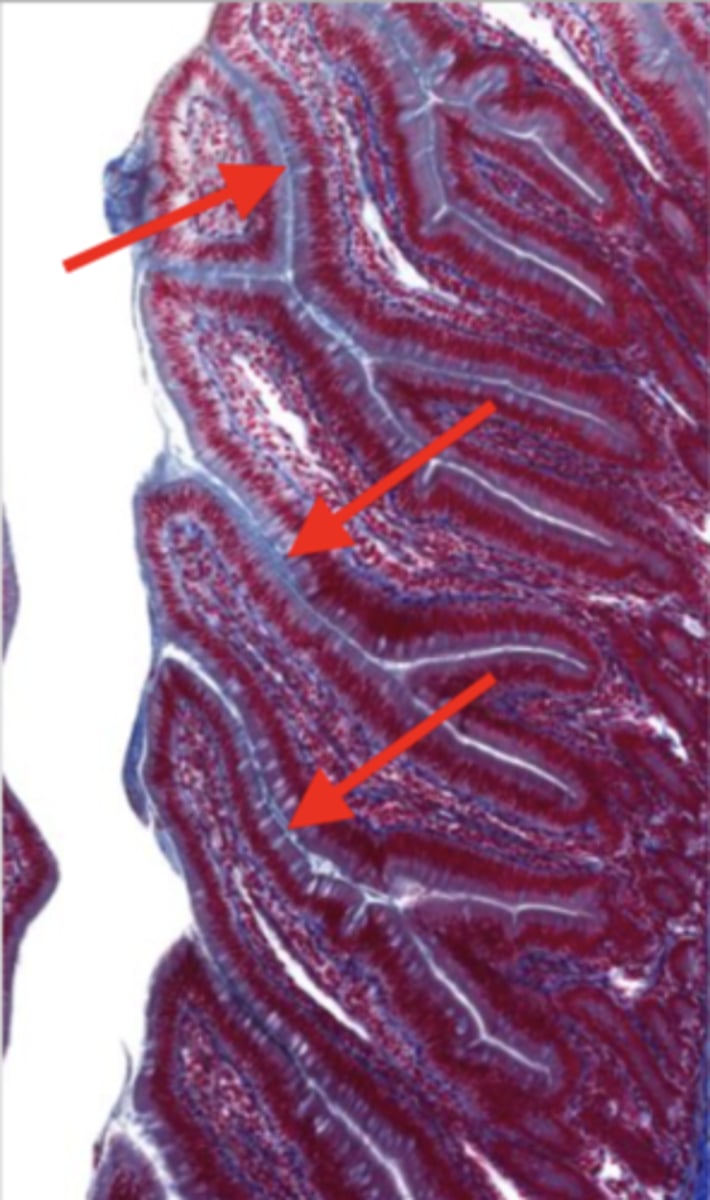

esophagus (histology)

lumen (esophagus)

mucosa (esophagus)

mucosal epithelium (esophagus)

stratified squamous epithelium

what kind of epithelium lines the mucosa of the esophagus?

lamina propria (esophagus)

muscularis mucosa (esophagus)

submucosa (esophagus)

contains glands and blood supply

muscularis externa (esophagus)

serosa/adventitia (esophagus)